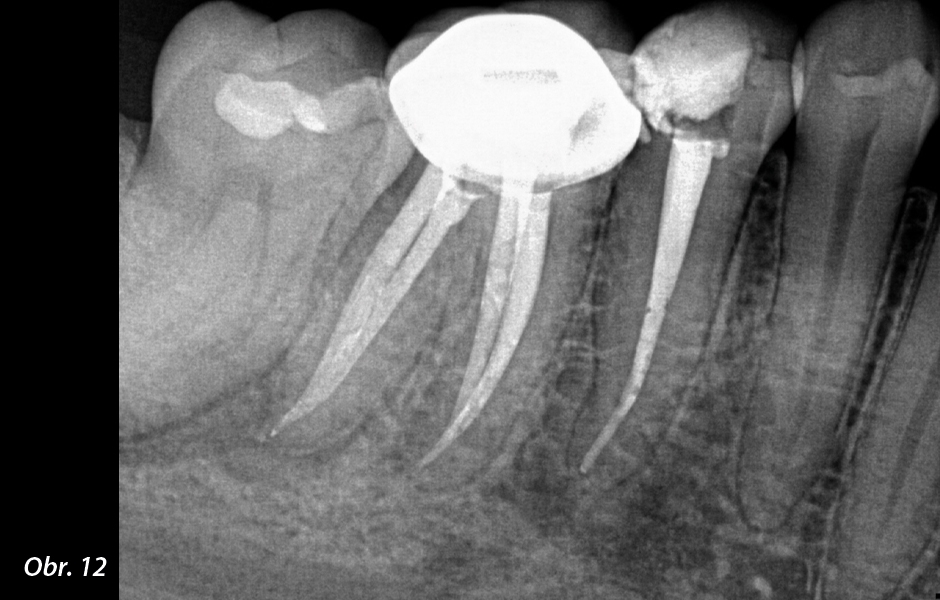

Co se stane, když ošetříte kořenový kanálek a léze se nehojí? Nejprve si musíte položit otázku: „Opravdu jsem úplně dezinfikoval zub? Našel jsem všechny kanálky a dostal jsem se na konec každého kanálku?“ Pamatujte, že milimetr je v endodontickém světě míle a pokud se nedostanete až k samotnému konci kanálku, stále zde mohou zůstat nějaké bakterie.

Nejprve tedy doporučuji skutečně posoudit váš dezinfekční protokol a mým návrhem bude vždy nejprve reendodoncie! Když zubaři často nedokážou vysvětlit, proč kořenový kanálek selhává, tak si automaticky myslí, že je zub prasklý, a začnou přemýšlet o nahrazení zubu. Ale to může být chybné! Nikdo není dokonalý a dokonce i ti nejlepší z nás musí provádět reendodoncie svých vlastních případů (zeptejte se mě, jak to vím!). Žádám vás tedy, abyste dali zubům šanci, a to obvykle znamená nejprve reendodoncii!

Pokud příznaky přetrvávají i po reendodoncii, přemýšlejte o dalších možnostech, jako je apexektomie. Existuje spousta anatomických studií, které ukazují, že v posledních 3 mm kořene mohou existovat rozsáhlé apikální ramifikace a isthmy. Pokud se tyto oblasti obtížně čistí, jedinou možností je fyzicky je odstranit apexektomií. Díky Bohu, že s tímto postupem přišli, protože nám umožňuje zachránit ještě více zubů.

Pamatujte, že apexektomie není něco, do čeho chcete jen tak skočit; chcete nejprve vyčerpat všechny své ortográdní možnosti. Při plánování léčby je třeba mít na paměti, že odstranění apexu ošetří pouze posledních 6 mm kořene, takže pokud máte podezření, že v celém kořeni jsou bakterie, musíte provést nejprve reendodontické ošetření. Vidíte, kam tím směřuji?